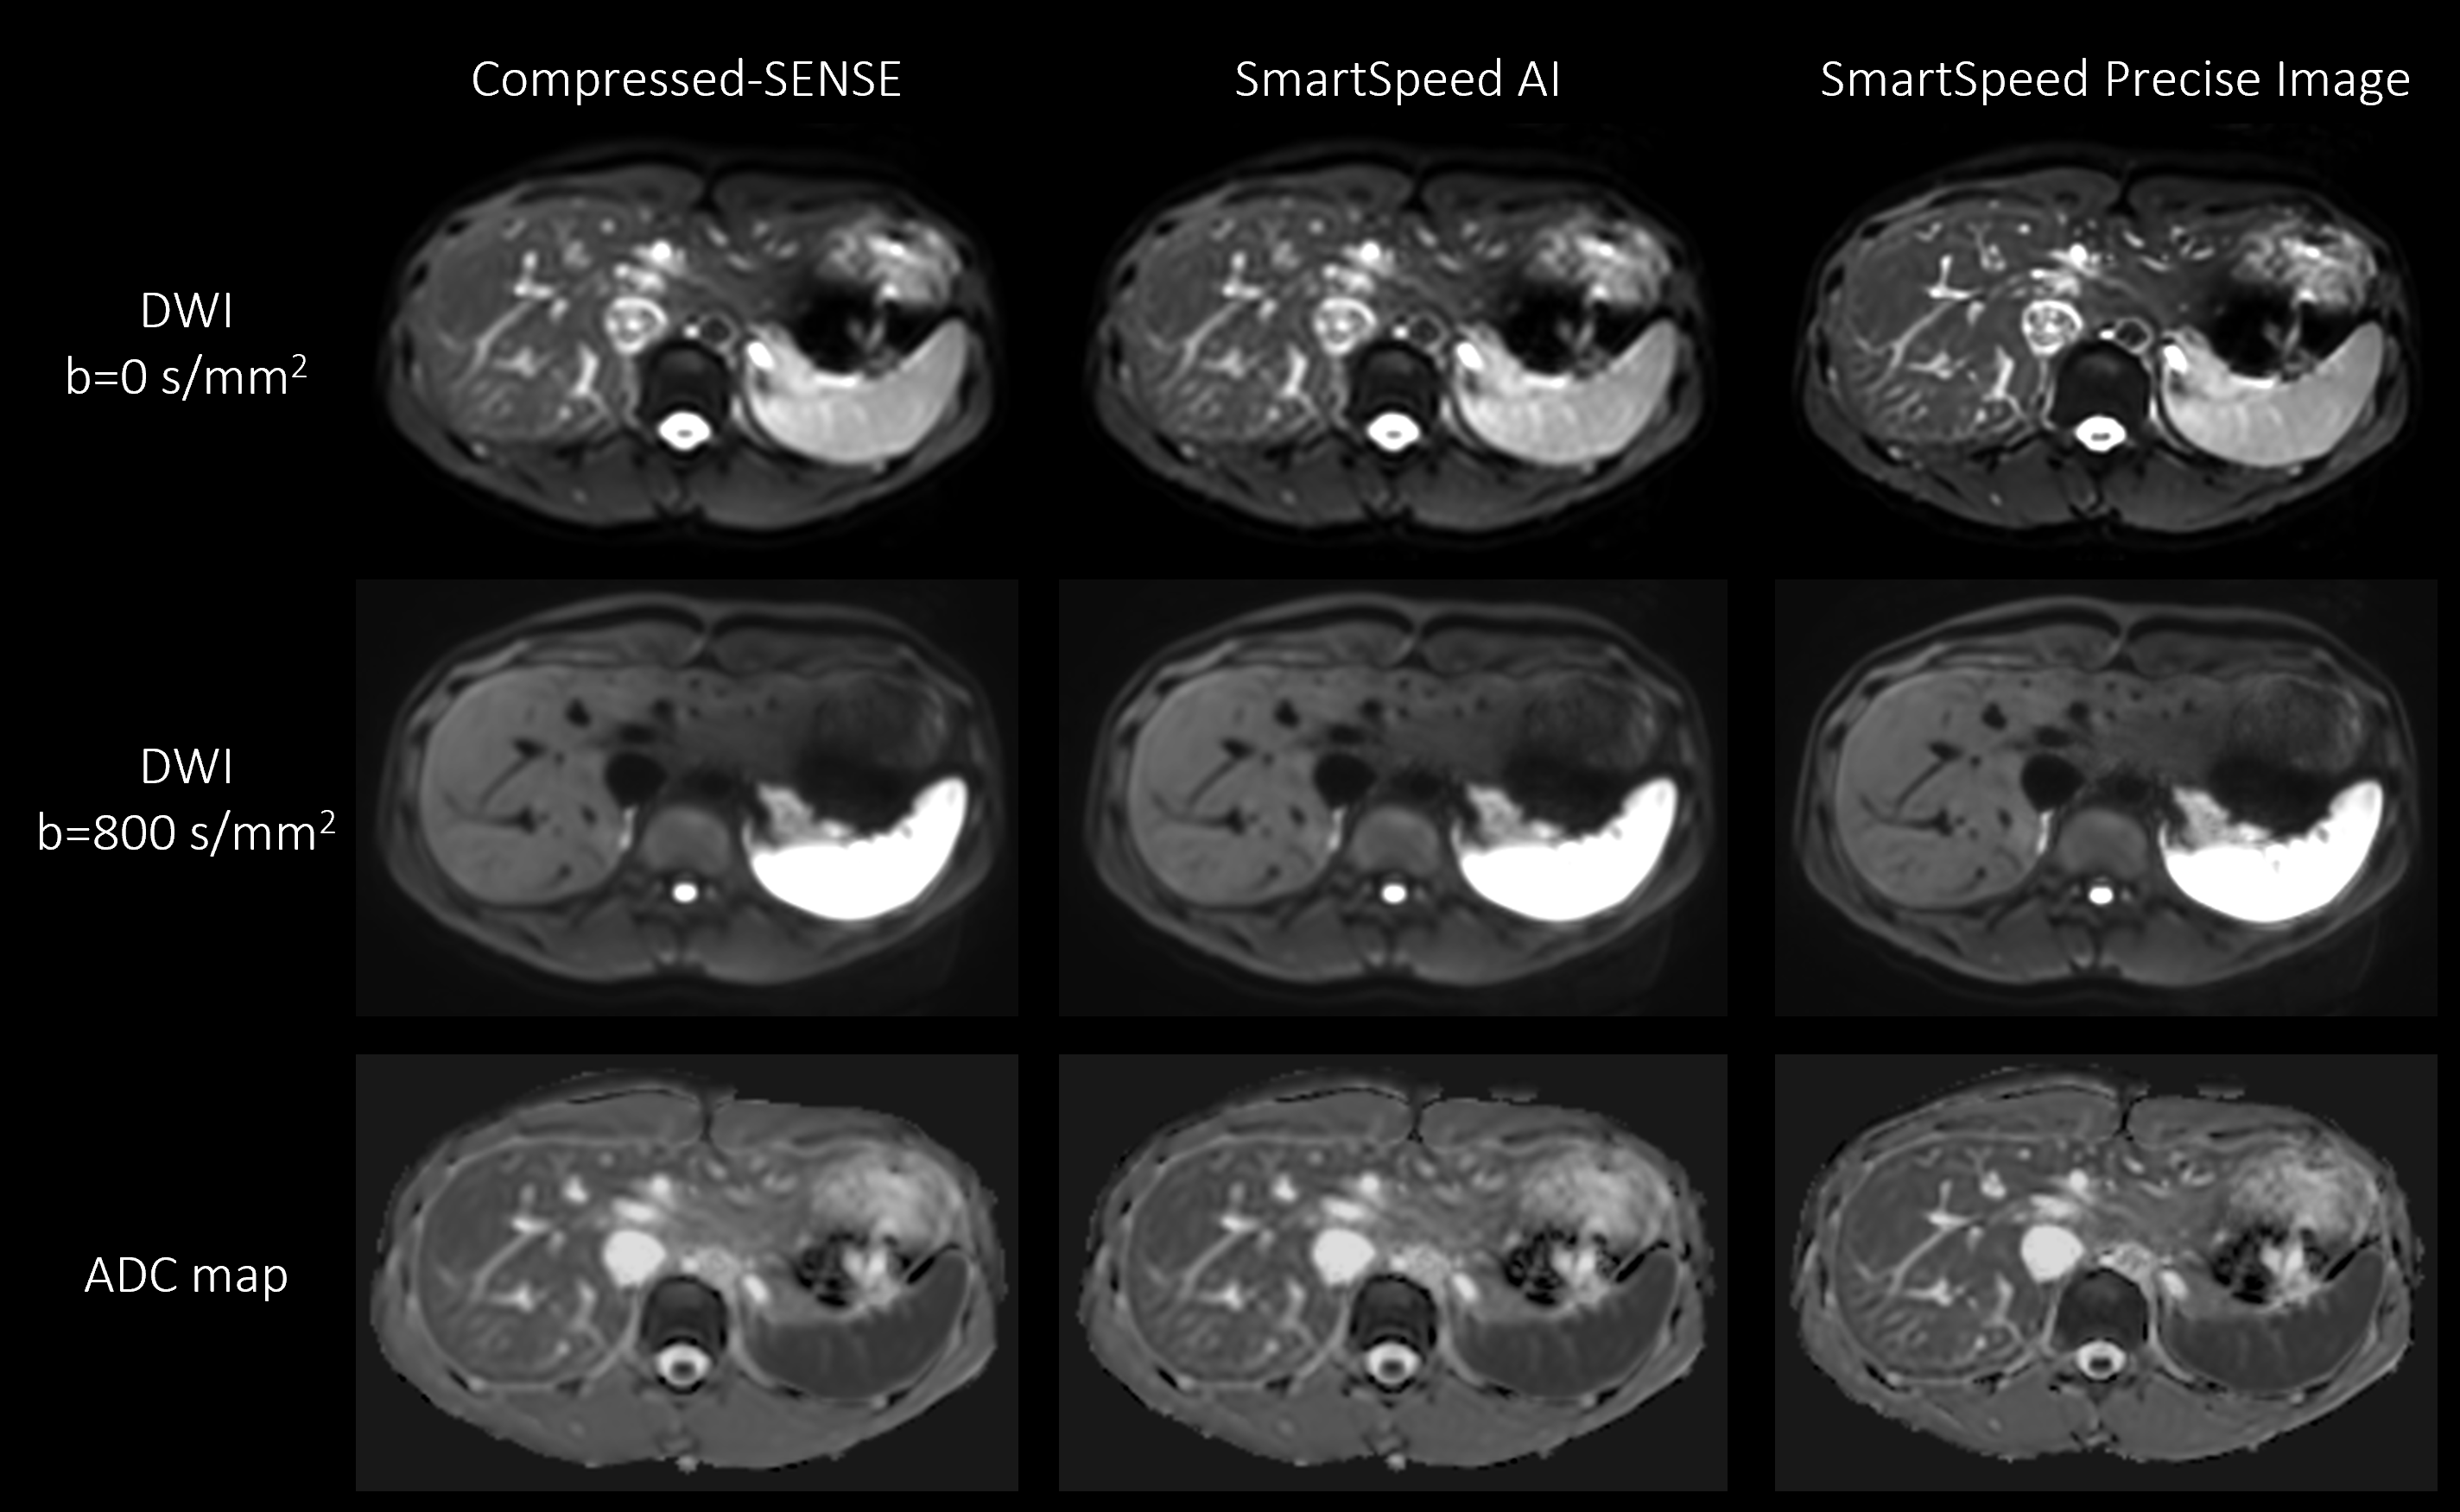

Figure 1 shows comparison of C-SENSE, SmartSpeed AI, and SmartSpeed Precise Image, all reconstructed with 1.6x1.6mm2 spatial resolution. Visually, SmartSpeed Precise Image showed improved sharpness in both b=0 and 800 s/mm2 images as well as ADC map. Figures 2 and 3 show comparisons of C-SENSE, SmartSpeed AI, and SmartSpeed Precise Image, all reconstructed with 0.83x0.83mm2 spatial resolution. The higher reconstruction resolution allowed SmartSpeed Precise Image to delineate vascular pattern even more clearly at b=0 s/mm2 and enhanced the edges at b=800 s/mm2. This resulted in sharper ADC map compared with C-SENSE and SmartSpeed AI, which used ZIP to improve the resolution. Figure 4 shows the enlarged view of b=0 s/mm2 images and ADC maps of C-SENSE, SmartSpeed AI, and SmartSpeed Precise Image, all reconstructed with 0.83x0.83mm2 spatial resolution. SmartSpeed Precise Image showed significantly improved visualization of vessels in both b=0 s/mm2 image and ADC map, which may enable evaluating smaller vascular patterns that were previously unobservable. Severe ringing artifacts caused by stomach contents and cerebrospinal fluid were significantly reduced by SmartSpeed Precise Image (Figures 2 and 4, yellow arrows). Figure 5 shows the histogram of the DWI pixel values and ADC values of the liver. In this subject, the mean pixel values for b=0 s/mm2 were 294.4, 294.2, 286.8 for C-SENSE, SmartSpeed AI, and SmartSpeed Precise Image, respectively, and for b=800 s/mm2 were 80.2, 83.0, 83.6, and the mean ADC values were 1.66, 1.61, 1.54 x10-3 mm2/s.

Figure 1. b = 0 (upper row), b = 800 s/mm2 (middle row) images, and ADC maps (lower row) of the liver in a healthy volunteer obtained with EPI-DWI, for C-SENSE (left), SmartSpeed AI (middle), and SmartSpeed Precise Image (right). All the images were reconstructed with 1.6x1.6 mm2 resolution.